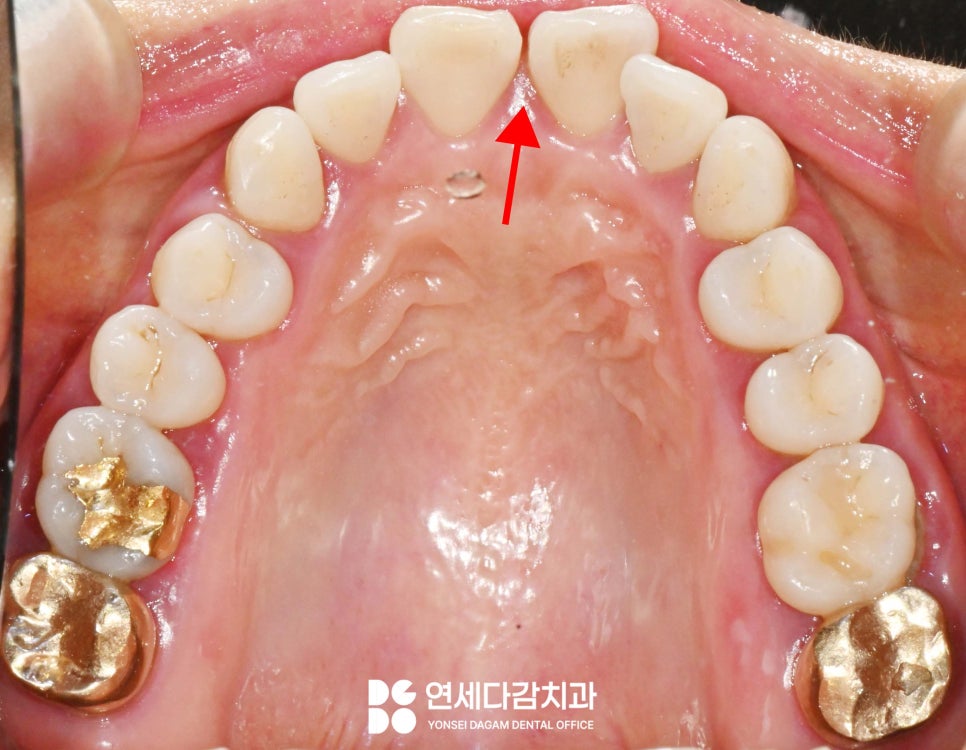

앞니 사이가 벌어져 있다면

어떤 치료를 선택 하시겠습니까?

앞니 사이가 벌어진 상태는

의학적으로 '치간이개(diastema)'

라고 부르는데,

이는 단순한 외관상의 문제가 아니라

때로는 기능적인 부분에도

영향을 미칠 수 있습니다.

특히 잘 보이는 곳이기 때문에

얼굴의 인상을 좌우하는

중요한 요소이기도 합니다.

양쪽 앞니의 폭경(width)을

정확히 측정하고

균형 있게 수복하는 것이 중요합니다.